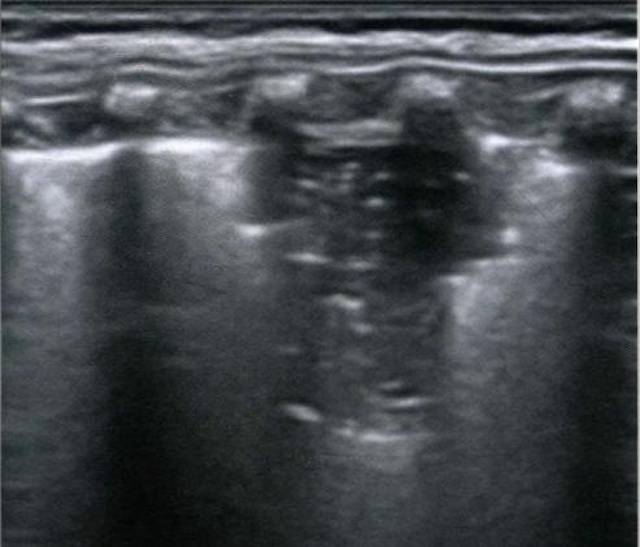

肺变实超声图

“肺部超声无辐射,适合需要反复检查的儿童,尤其是新生儿和婴幼儿,避免了辐射暴露带来的潜在风险。”黄永说,其操作便捷灵活,可在床旁快速进行,无需搬运患儿,这对于病情危重、无法配合移动的孩子来说尤为重要。